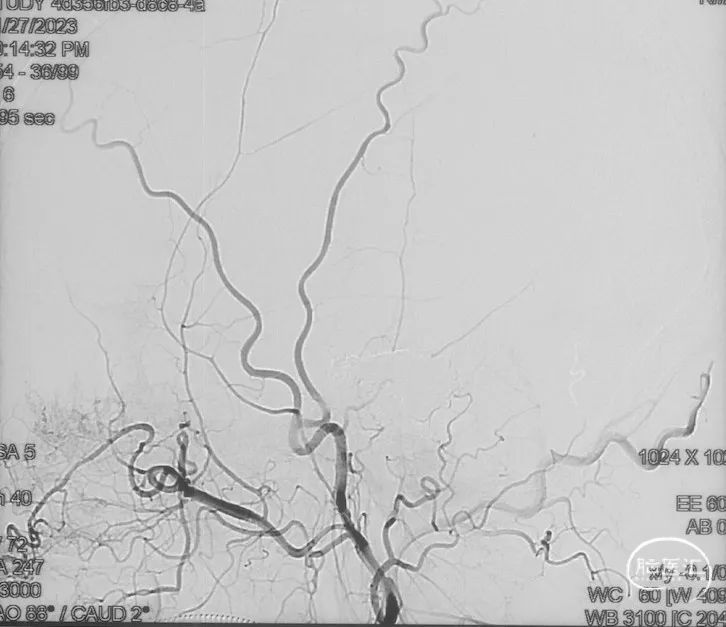

术前造影

证实为TDAVF,为岩上窦型。R-ECA正侧位见右侧脑膜中动脉分支、枕动脉分支、颞浅动脉分支向瘘口供血,经幕上迂曲扩张的静脉、中脑周围静脉、基底静脉向深部静脉引流。

R-ICA正侧位见右侧脑膜垂体干向瘘口供血

L-ICA正侧位见左侧脑膜垂体干分支向瘘口供血

L-ECA正侧位未见向瘘口供血

L-VA、R-VA正侧位右侧小脑上动脉脑膜支向瘘口供血

选取工作角度,正侧位造影